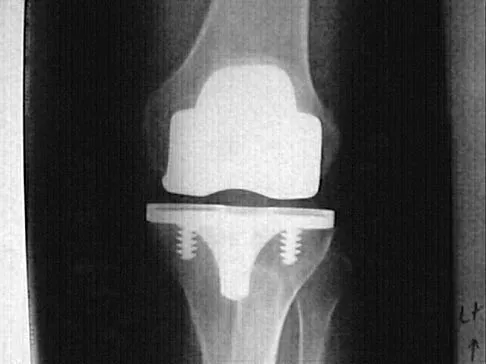

Question 41

Figures 5a and 5b show the radiographs of an active 52-year-old man who has increasing knee pain and progressive varus deformity after undergoing total knee arthroplasty 7 years ago. Examination reveals a small effusion, but he has good motion and stability. What is the most likely diagnosis?

Explanation